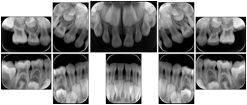

3. A dental provider wishes to capture a series of DICOM IO images for the patient’s dentition. The tooth morphology, teeth are divided into molars, premolars, canines and incisors, and a number of images for each jaw. The anatomic information was captured utilizing the triplet of schema. This standard code sequence is based on ISO 3950-2010, Dentistry - Designation system for teeth and areas of the oral cavity.

Every IO image should have anatomic information either through the primary or modifier sequence.

In most standard cases, images are oriented in structured layouts. These structured displays are useful to be shared between providers for reference purposes.

Table OO.1.1-1 shows structured display standard templates, where Viewset ID is based on the Japanese Society for Oral and Maxillofacial Radiology (JSOMR) classification provided by JIRA (Japan Medical Imaging and Radiological Systems Industries Association, www.jira-net.or.jp). Expected or typical teeth to be imaged location, region and designation codes are based on ISO 3950-2010, Dentistry - Designation system for teeth and areas of the oral cavity. For all the hanging protocols listed in OO.1.1-1, the value to use for Hanging Protocol Creator (0072,0008) is "JSOMR" and the value to use for Hanging Protocol Name (0072,0002) does not include "JSOMR" (e.g., "DL-S001A", not "JSOMR DL-S001A").